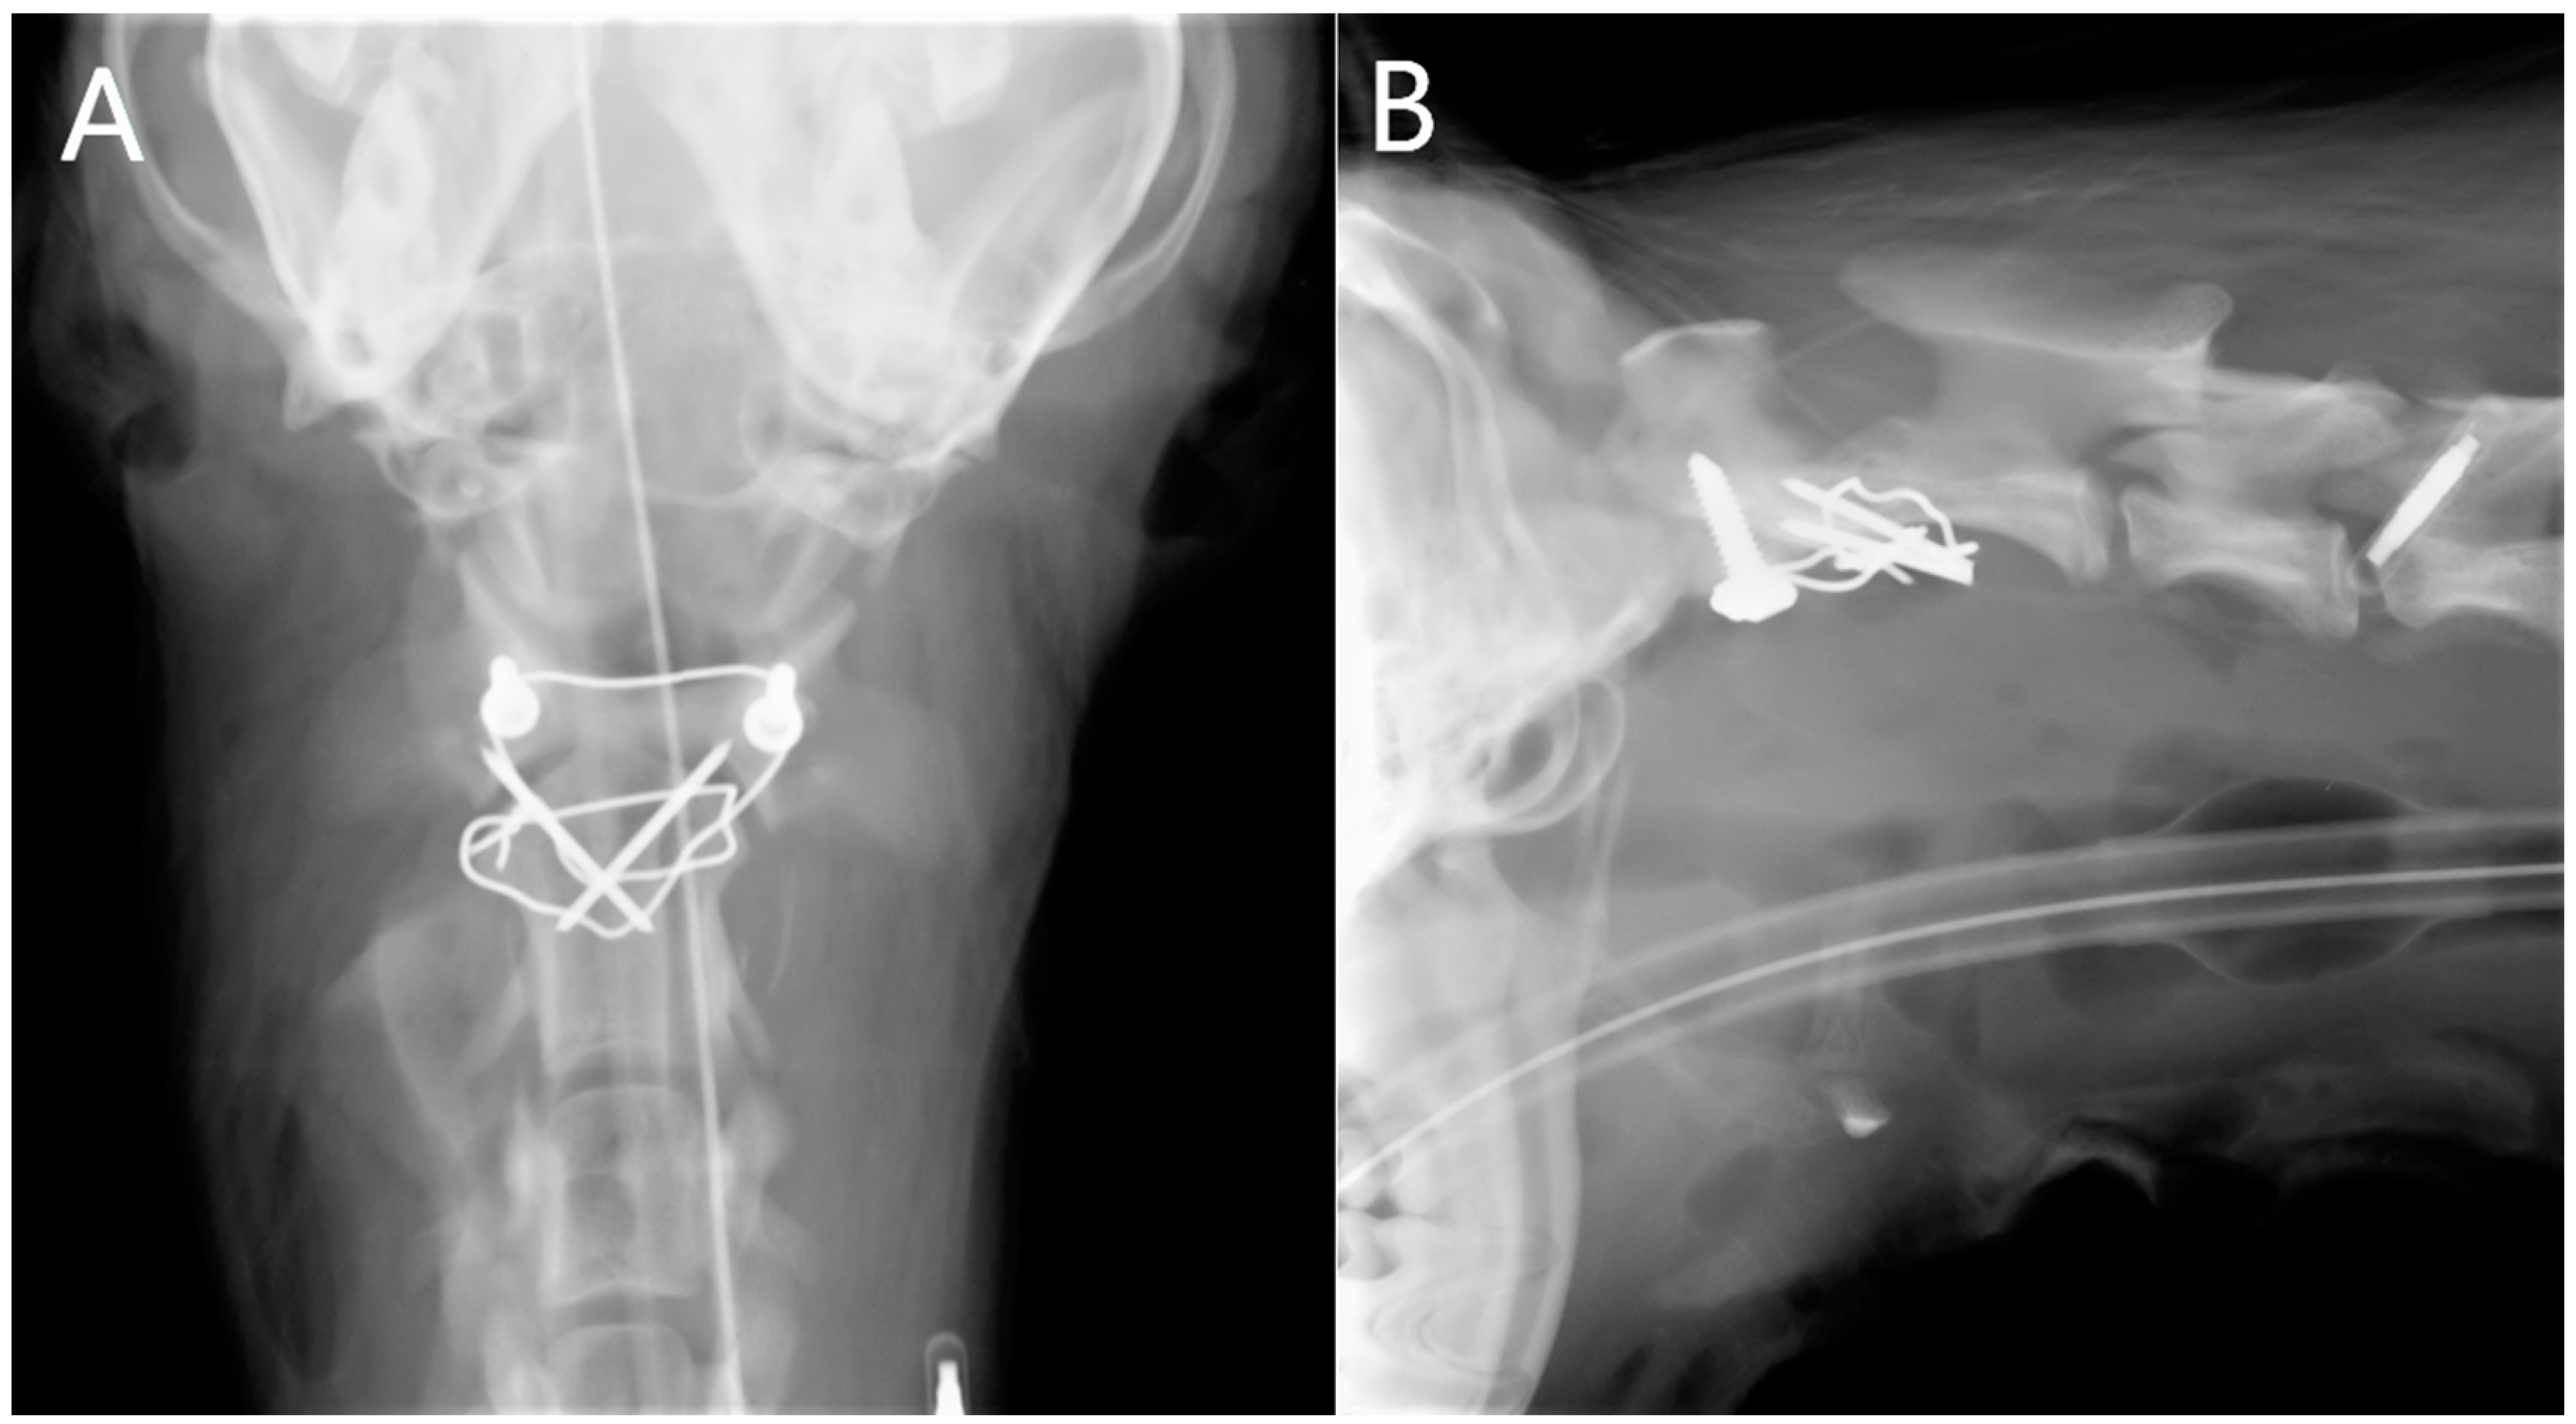

2.4.1. Radiographs

2.4.2. Computed Tomography